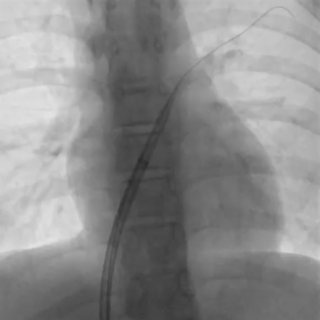

送入输送系统

沿导丝送入输送鞘

左盘展开

DSA下牵拉成型线使左盘成型,超声可见左盘后撤贴靠房间隔